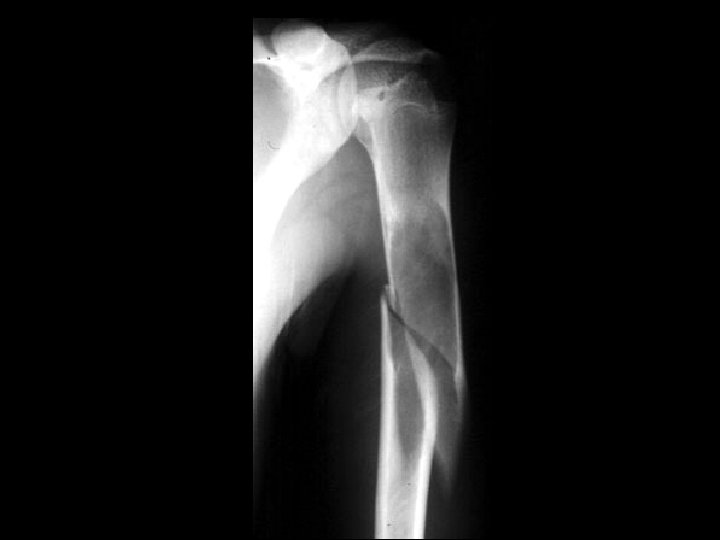

Lymphoma • Findings: – Permeative lesion of the proximal humerus • ddx: – Multiple myeloma – Metastasis – MFH – Infection – Langerhan’s cell histiocytosis